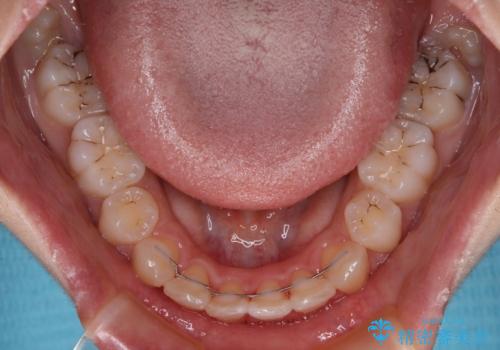

指が入るくらいに隙間のある上下前歯 抜歯矯正で横顔の印象が大きく改善

舌の突出癖などにより、上下前歯の間に指が入るくらい隙間のできる状態でした。

舌の突出癖は十分に改善されたとは言えない状態でしたので、今後の後戻り防止対策として、経過観察中も舌のトレーニング指導を行っていくこととなります。